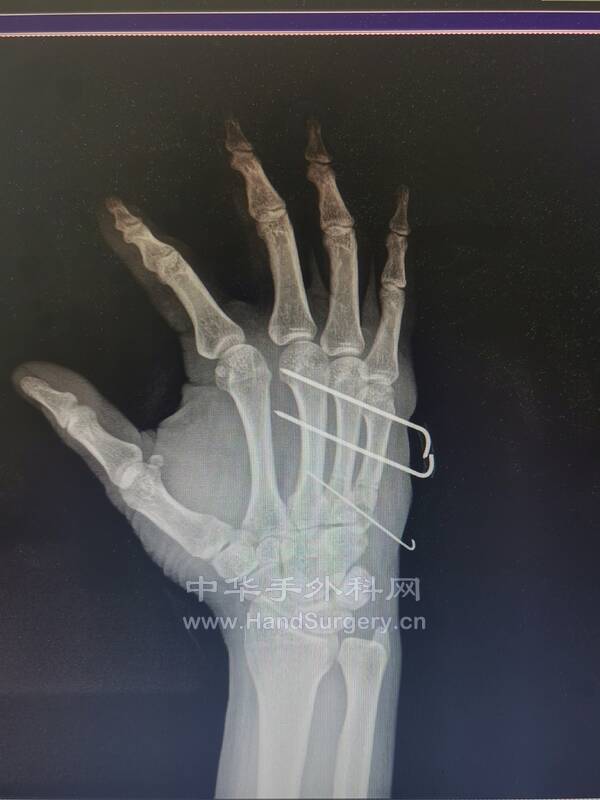

因为今天又做了一例

使用同样的方法

很快,微创,高效

今天的病例

这种关节内骨折的移位可能与Bennett骨折相似

因为尺侧腕伸肌腱的牵拉产生一种很大的使掌骨干向近端移位的趋势

与Bennett骨折中拇指掌骨的移位相似

这种骨折通常可以通过牵引复位,经皮穿针固定

对于哪些未能早期发现而在移位位置愈合的骨折,应通过愈合部位的截骨或关节切除成形术加以矫正

微信图片_20220614225637.jpg

微信图片_20220614225624.jpg